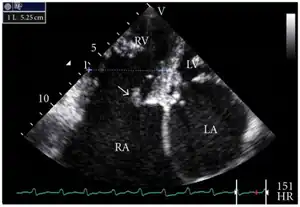

Transthoracic echo: TR (arrow) -

Echocardiogram: severe TR